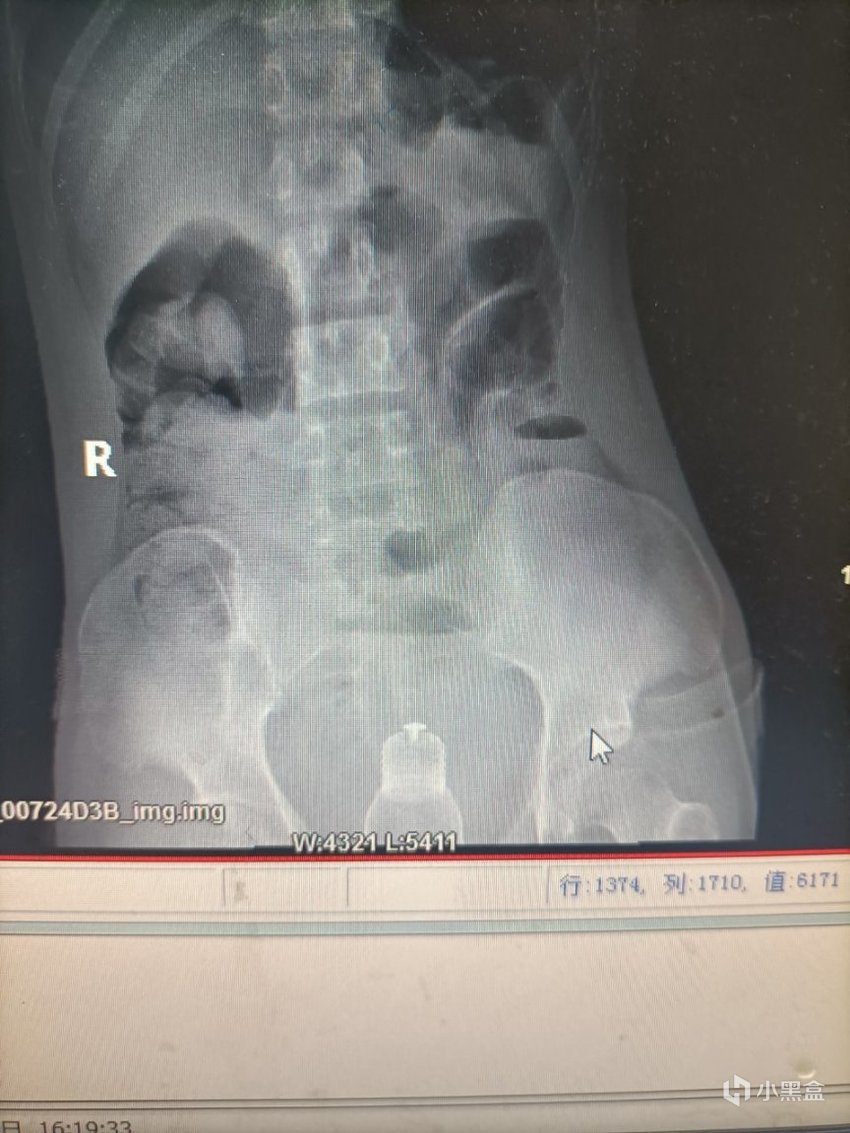

上面有我接診過的患者,也有來源網絡的圖片。但是這種誤入體內的異物,可能有電子產品或者瓶子,甚至也有活物進入的情況。大多數直腸異物發生sex的過程中,被取出的異物包括但不限於按摩棒,橡膠聖劍、高爾夫球、白熾燈等等(也經常有毒販通過包裝好的袋裝毒品藏入胃裏或者直腸裏來販毒)。有一些異物可能一開始已經被完全容納進去,深入體內後難以取出。

比如這位患者在嘗試用夾鉗自救取出異物,可惜一起折戟在體內了不得已就診。

直腸異物典型症狀就是排便困難、腹痛、便血,甚至腸梗阻。如果嘗試自救,反覆磨蹭還可能導致肛管、直腸部分的黏膜水腫和肌肉痙攣,進而更難取出異物。而且最好不要輕易嘗試在不確定異物種類和位置的情況下,做直腸檢查。要不然容易導致異物破裂,造成二次傷害。

一般在直腸鏡下通過夾鉗和牽引取出位置較低的異物,高位的就需要結腸鏡和手術取出了。總結來說,這屬於人禍導致的,無論是否是自己主動塞進去異物,最後都需要儘早解決。